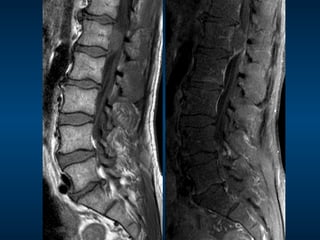

•  68M

•  Sudden onset bilateral leg pain and

weakness

MRI

•  Dx: Cauda equina syndrome

•  Cause: massive sequestration

•  Other causes:

– Tumour

•  Primary of lower cord, nerve, dura, vertebral

body

•  Secondary

– Trauma